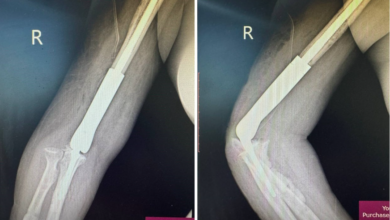

Дээд мөчний ясны хавдрын хиймэл үе суулгах мэс заслыг анх удаа хийлээ

Улсын нэгдүгээр төв эмнэлгийн ХҮСҮСТ-ийн дарга М.Отгонбаяраар ахлуулсан үений мэс заслын баг Монгол Улсад анх удаа атгаал ясны дээд хэсгийн гуравны…